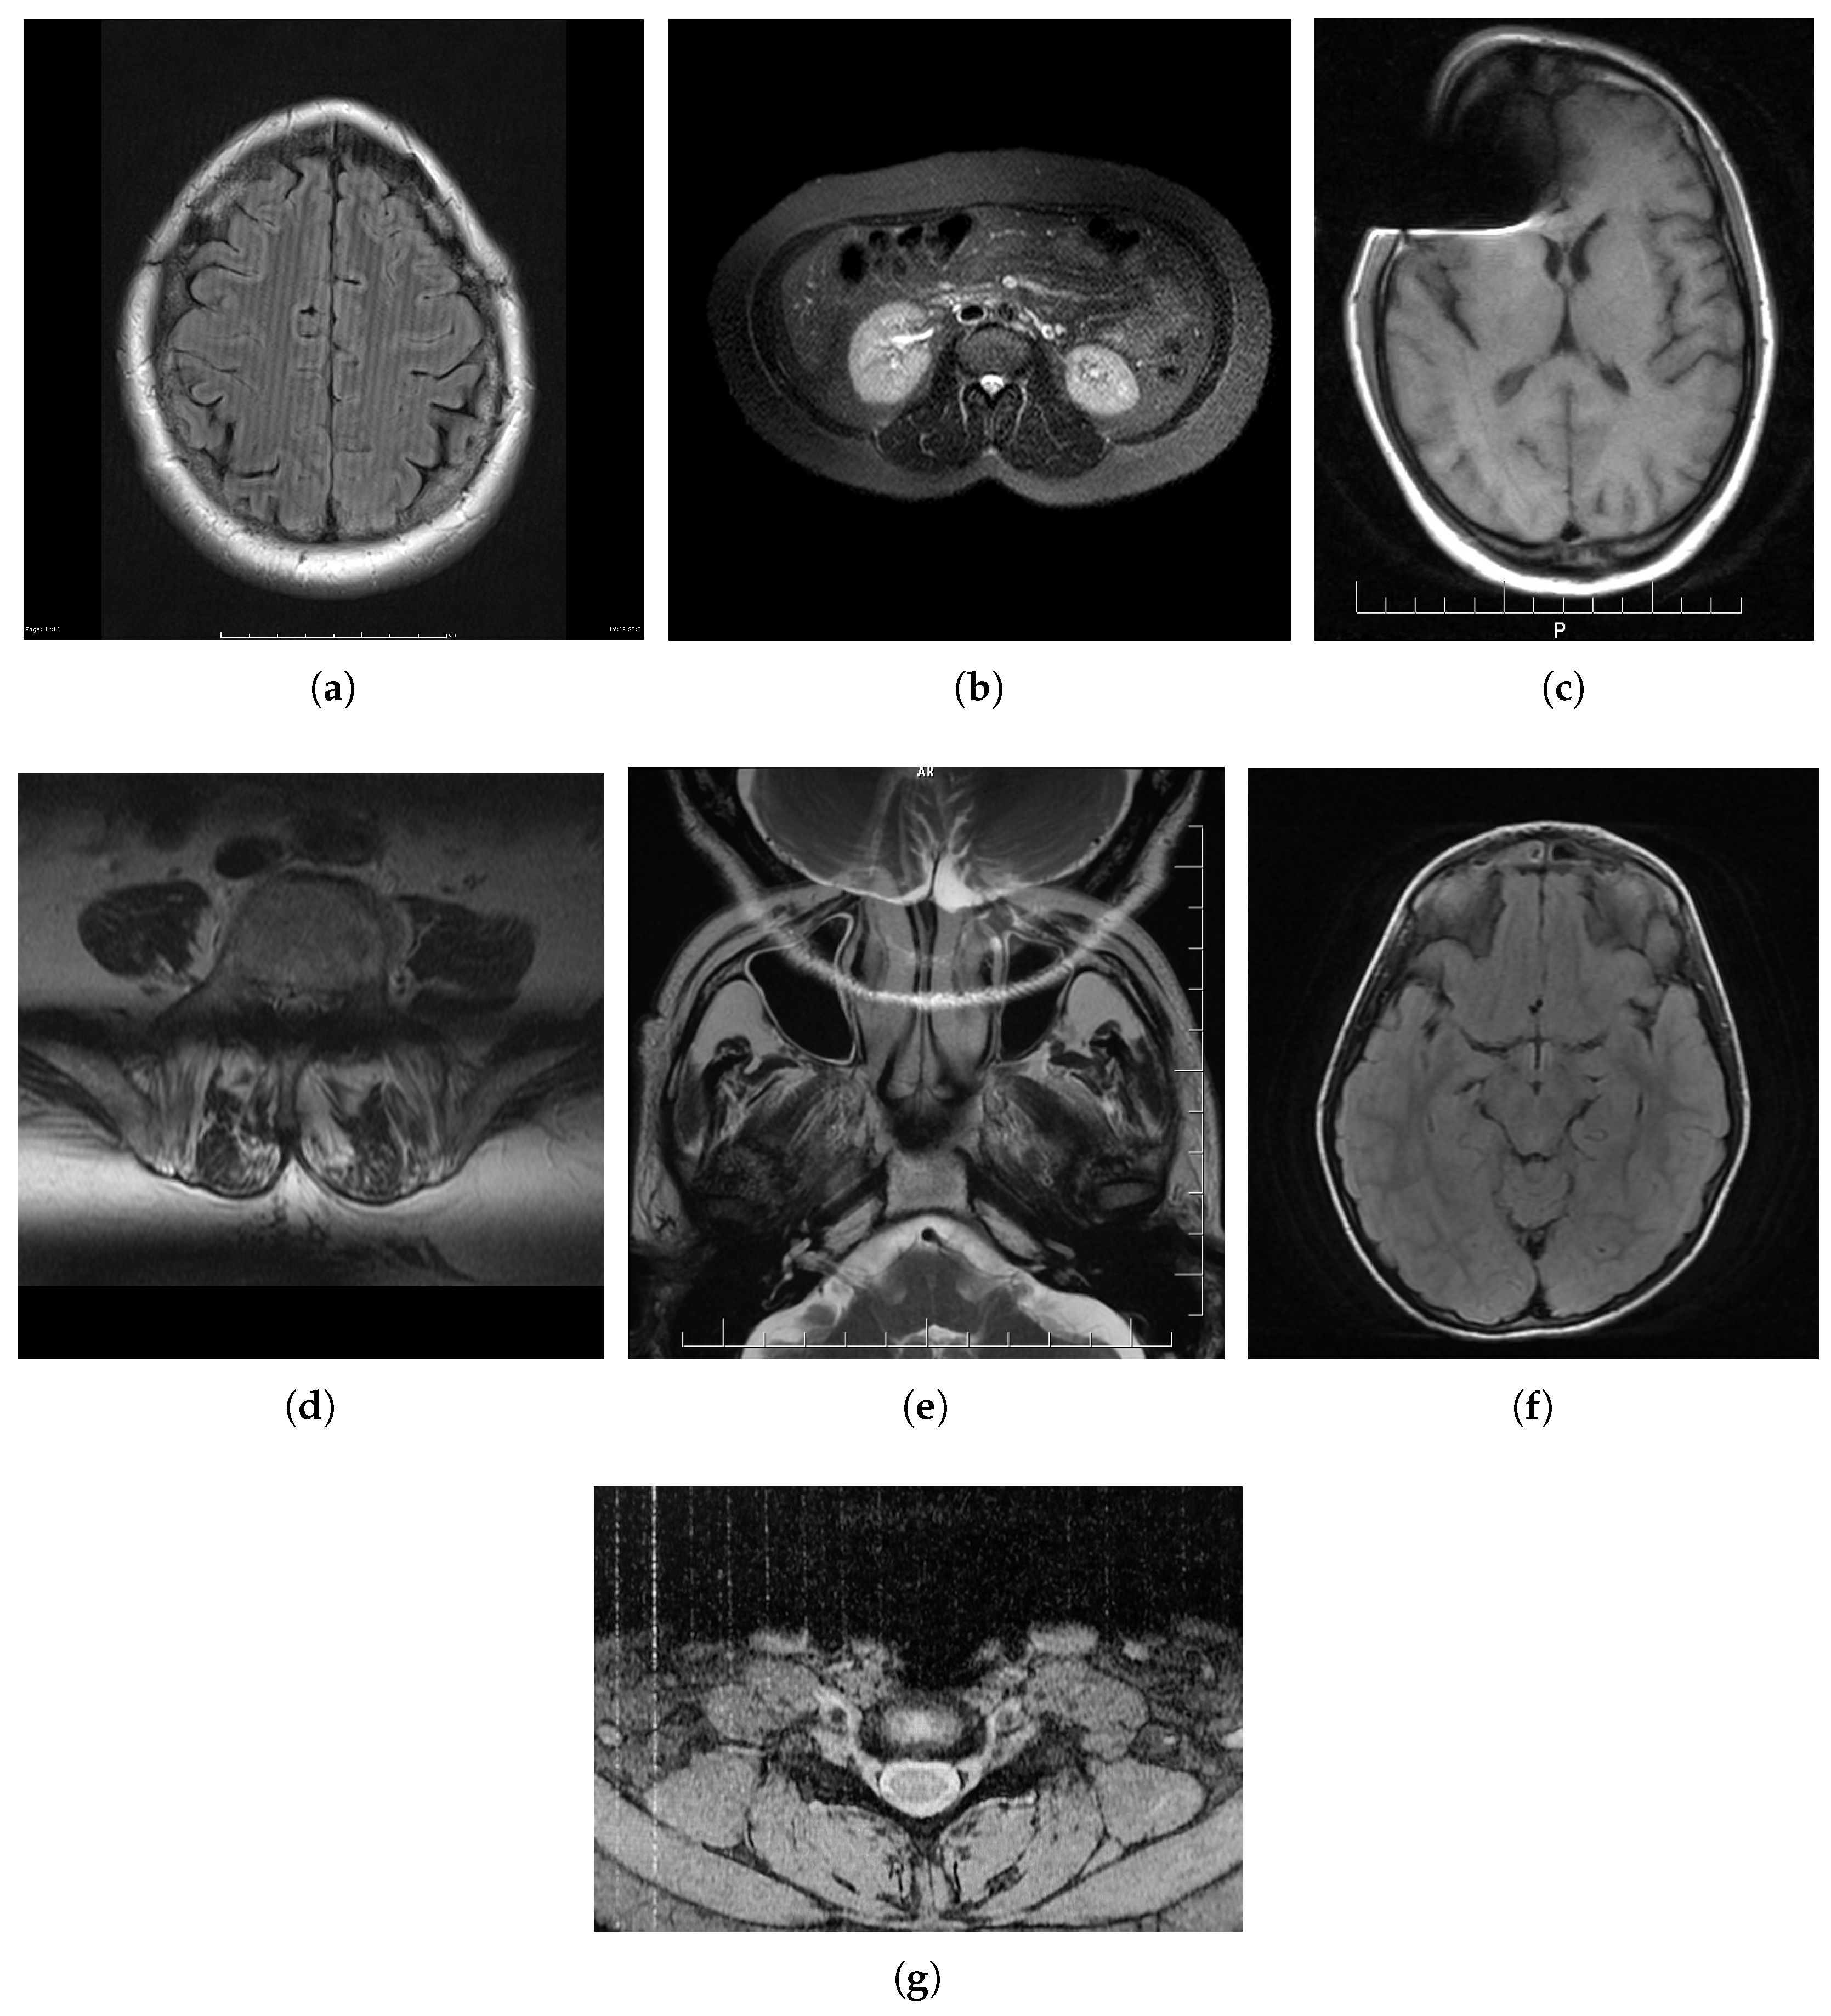

2. MRI Distortions

2.1. Spike (Herringbone) Artifact

2.2. Zipper Artifact

2.3. Ghosting

2.4. Blurring

2.5. Aliasing Artifacts

2.6. Gibbs Effect

2.7. Slice-Overlap Artifact

2.8. Gradient-Related Distortion

2.9. Parallel Imaging Artifact

2.10. Susceptibility Effect